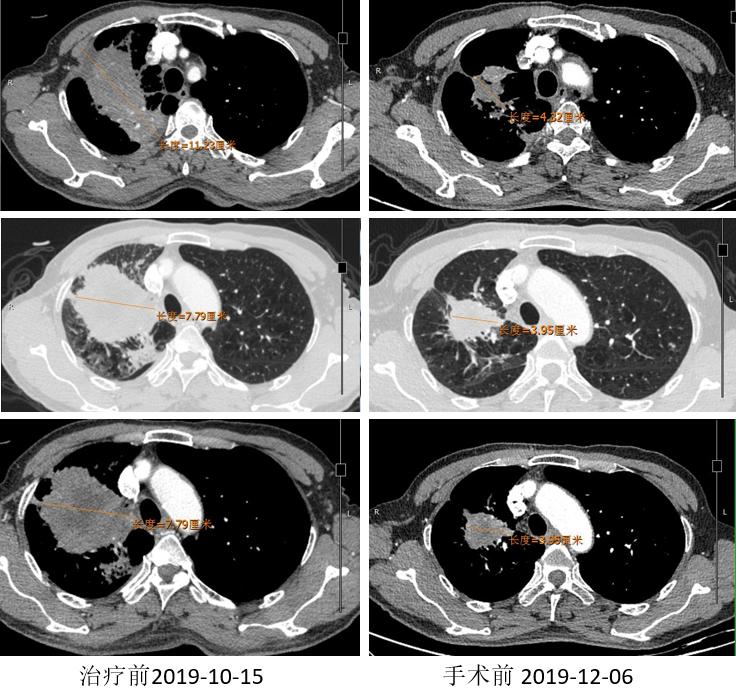

胸部CT

外周淋巴结CT